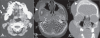

Congenital infiltrating lipomatosis of the face is a rare condition characterized by diffuse fatty infiltration of the facial soft tissues. There may be muscle involvement along with associated bony hyperplasia. It is a type of lipomatous tumor that is congenital in origin; it is rare and seen usually in childhood. We recently saw an 11-year-old girl with this condition. She presented with a swelling of the right side of the face that had been present since birth; there were typical findings on plain radiographs, CT, and MRI. The patient underwent cosmetic surgery. Histopathological examination showed mature adipocytes without any capsule.